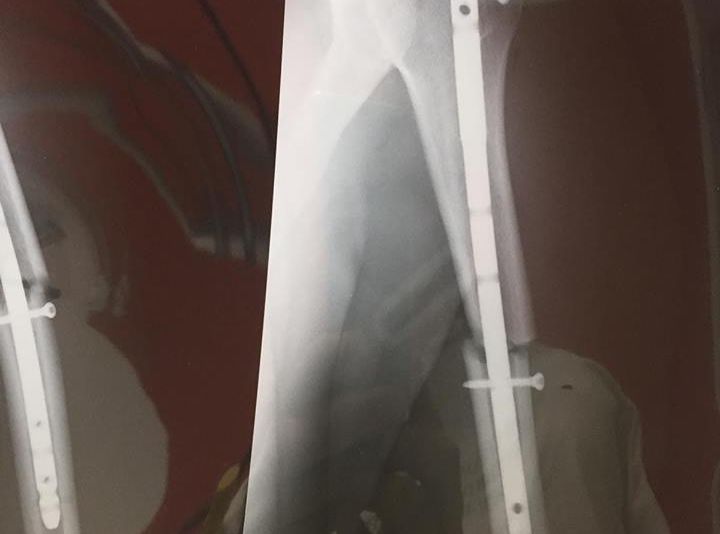

Rider-ul sătmărean de la Autonet Motorcyle Team a căzut de pe motocicletă și a suferit o fractură de humerus.În weekend, în cadrul unei sesiuni foto, Mani Gyenes a căzut de pe motocicletă, s-a răstogolit de câteva ori în aer, iar la aterizare a căzut pe umăr și a suferit fractură de humerus. În funcție de perioada de recuperare, Mani Gyenes va particpa sau nu la DAKAR 2019.

- ”Anul acesta, ultimele saptamani dinaintea plecarii catre Raliul Dakar vor decurge intr-un mod diferit. In weekend, in timpul unei sesiunii foto, am suferit o fractura de humerus si acum ma concentrez pe recuperare. Voi face tot ce imi sta in putinta sa ajung la finisul din Lima” este mesajul postat de Mani pe pagina sa de Facebook.